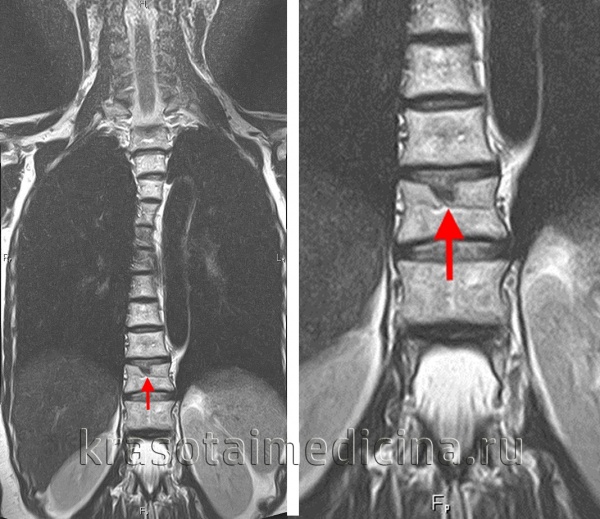

Наличие в клинике выраженного болевого синдрома, не типичного для грыжи Шморля, указывает на возможное образование грыжи межпозвоночного диска. Поскольку последняя не визуализируется при помощи рентгенографии, в таких случаях показана МРТ позвоночника, а при невозможности ее проведения — КТ позвоночника.

Золотым стандартом в диагностике компрессионной миелопатии является выполнение КТ и МРТ позвоночника. На снимках можно отчетливо увидеть не только причины, приведшие к сдавлению, но и состояние тканей мозга.

При невозможности произвести томографическое исследование, а также при подозрении на перелом позвоночника или вывих позвонков, используется рентгенография позвоночного столба в трех проекциях. По показаниям проводится люмбальная пункция с исследованием спинномозговой жидкости. Может быть использована миелография – особый рентгенологический метод, в основе которого лежит введение в субарахноидальное пространство контраста. После распределения красящего вещества производится серия снимков, которые позволяют определить на каком уровне произошло сдавление спинного мозга.